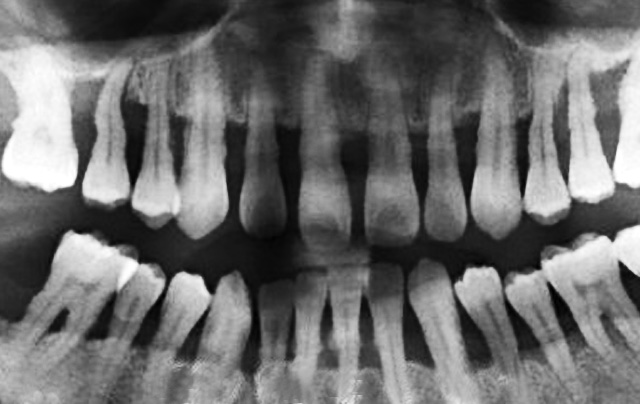

1、牙齿矫正会导致牙龈萎缩、牙槽骨吸收?

整牙时可能会出现牙龈萎缩的情况,主要是以下几种原因造成的:

A.个人牙周情况和清洁问题。一般牙周差的人需要在矫正前先做牙周治疗,牙周不好的人会比一般人更容易牙龈萎缩。其次就是正畸期间,如果不好好刷牙也会引起龋齿、牙龈萎缩,甚至出现牙槽骨吸收等情况。

B.随着年龄增长,牙龈会自然萎缩,所以在年龄偏大的患者出现的概率比较大。

需要特别提醒大家,正畸治疗需要找专业的医生,否则后果不堪设想,比如加力过于频繁、加力过大等会对牙龈产生不良影响。

综合上述,如果您选择的是有丰富经验的正畸医生,并认真听从医嘱,是无需担心牙龈萎缩、牙槽骨吸收等问题的。